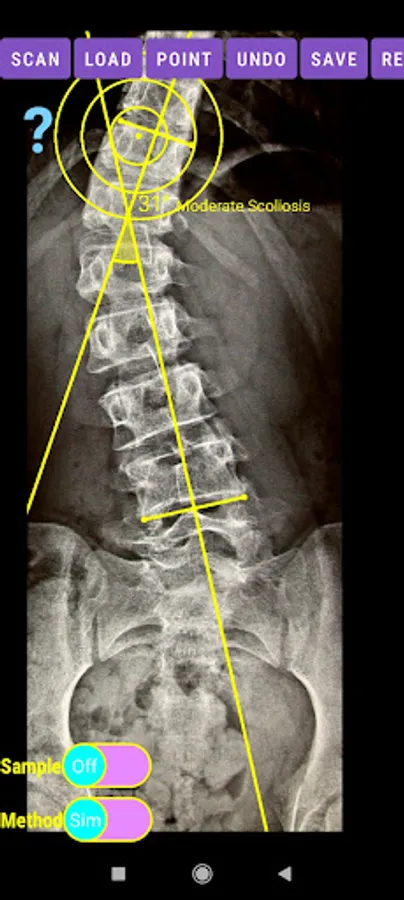

-Offers a very convenient way to determine the most accurate possibly way at once. By marking four points at the same X-ray, at each spine the App calculates the Cobb angle. In cases where values are out of normal ranges, the scoliosis is categorized according to measured angle as mild, moderate, severe. To simplify the process and to minimize inter-observer errors usually by not selecting the actual end vertebra, the app offers also in ext mode the ability to draw the vertical reference line through the patient’s sacrum and to identify more easily the end vertebrae (ext method).

The app offers a very convenient way to asses spinal deformity by measuring the Cobb angle. The first thing is to load one image from your photo library or capture a photo from x-rays photos of a patient. The app offers two measuring methods, the simple (Sim.) and the extended (Ext.). By clicking the relevant option, the option is highlighted and the respective method is activated.